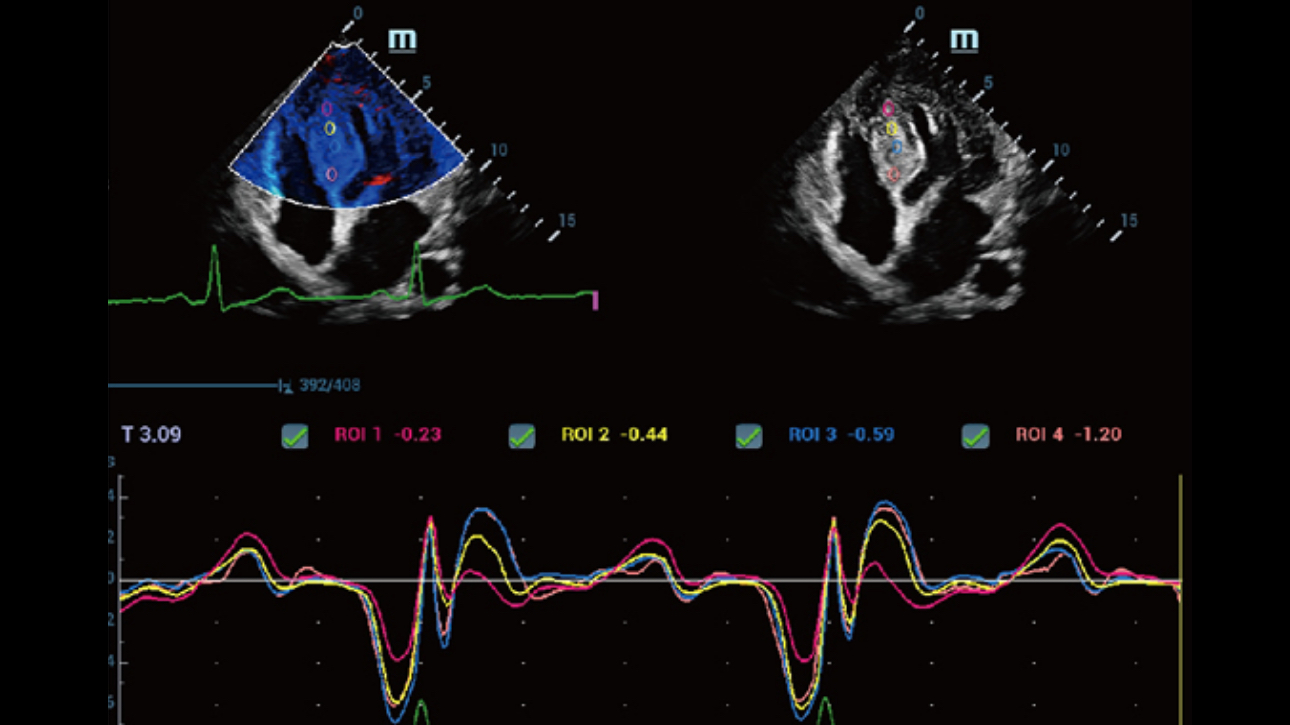

Powered by the channel data based ZST+ platform, the new Resona 6 with Zone Intelligence builds up a truly smart mechanism to deliver a new level of intelligence.The core of Zone Intelligence is deep learning that is based on big data base and Ultrasound expertise

As a result, it is able to provide multiple intelligent retrospective processing, leading to efficient and effective image visualization, plane recognition, measurement, and image enhancement .